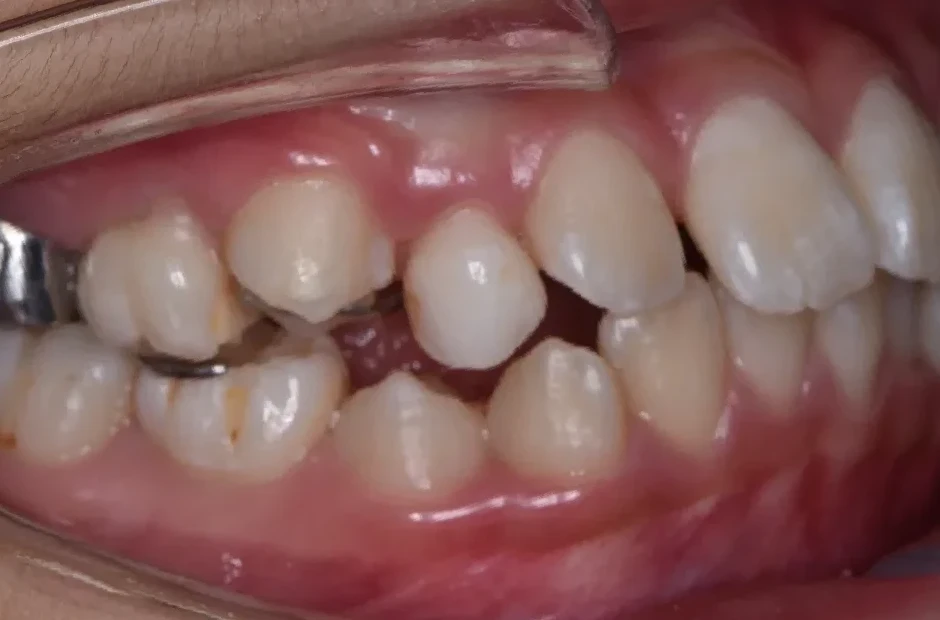

治療症例

ブラケット矯正

前歯部反対咬合

| 診断名・主訴 | 前歯部反対咬合 |

|---|---|

| 年齢・性別 | 14歳・男性 |

| 治療期間・回数 | 1年2か月 |

| 治療に用いた主な装置 | ブラケット矯正 |

| 抜歯部位 | なし |

| 治療費 | 60万円(税抜) |

| リスク・副作用 | 装置による違和感・疼痛・歯肉退縮・歯根吸収・虫歯のリスクなど |

治療前

治療中

治療後